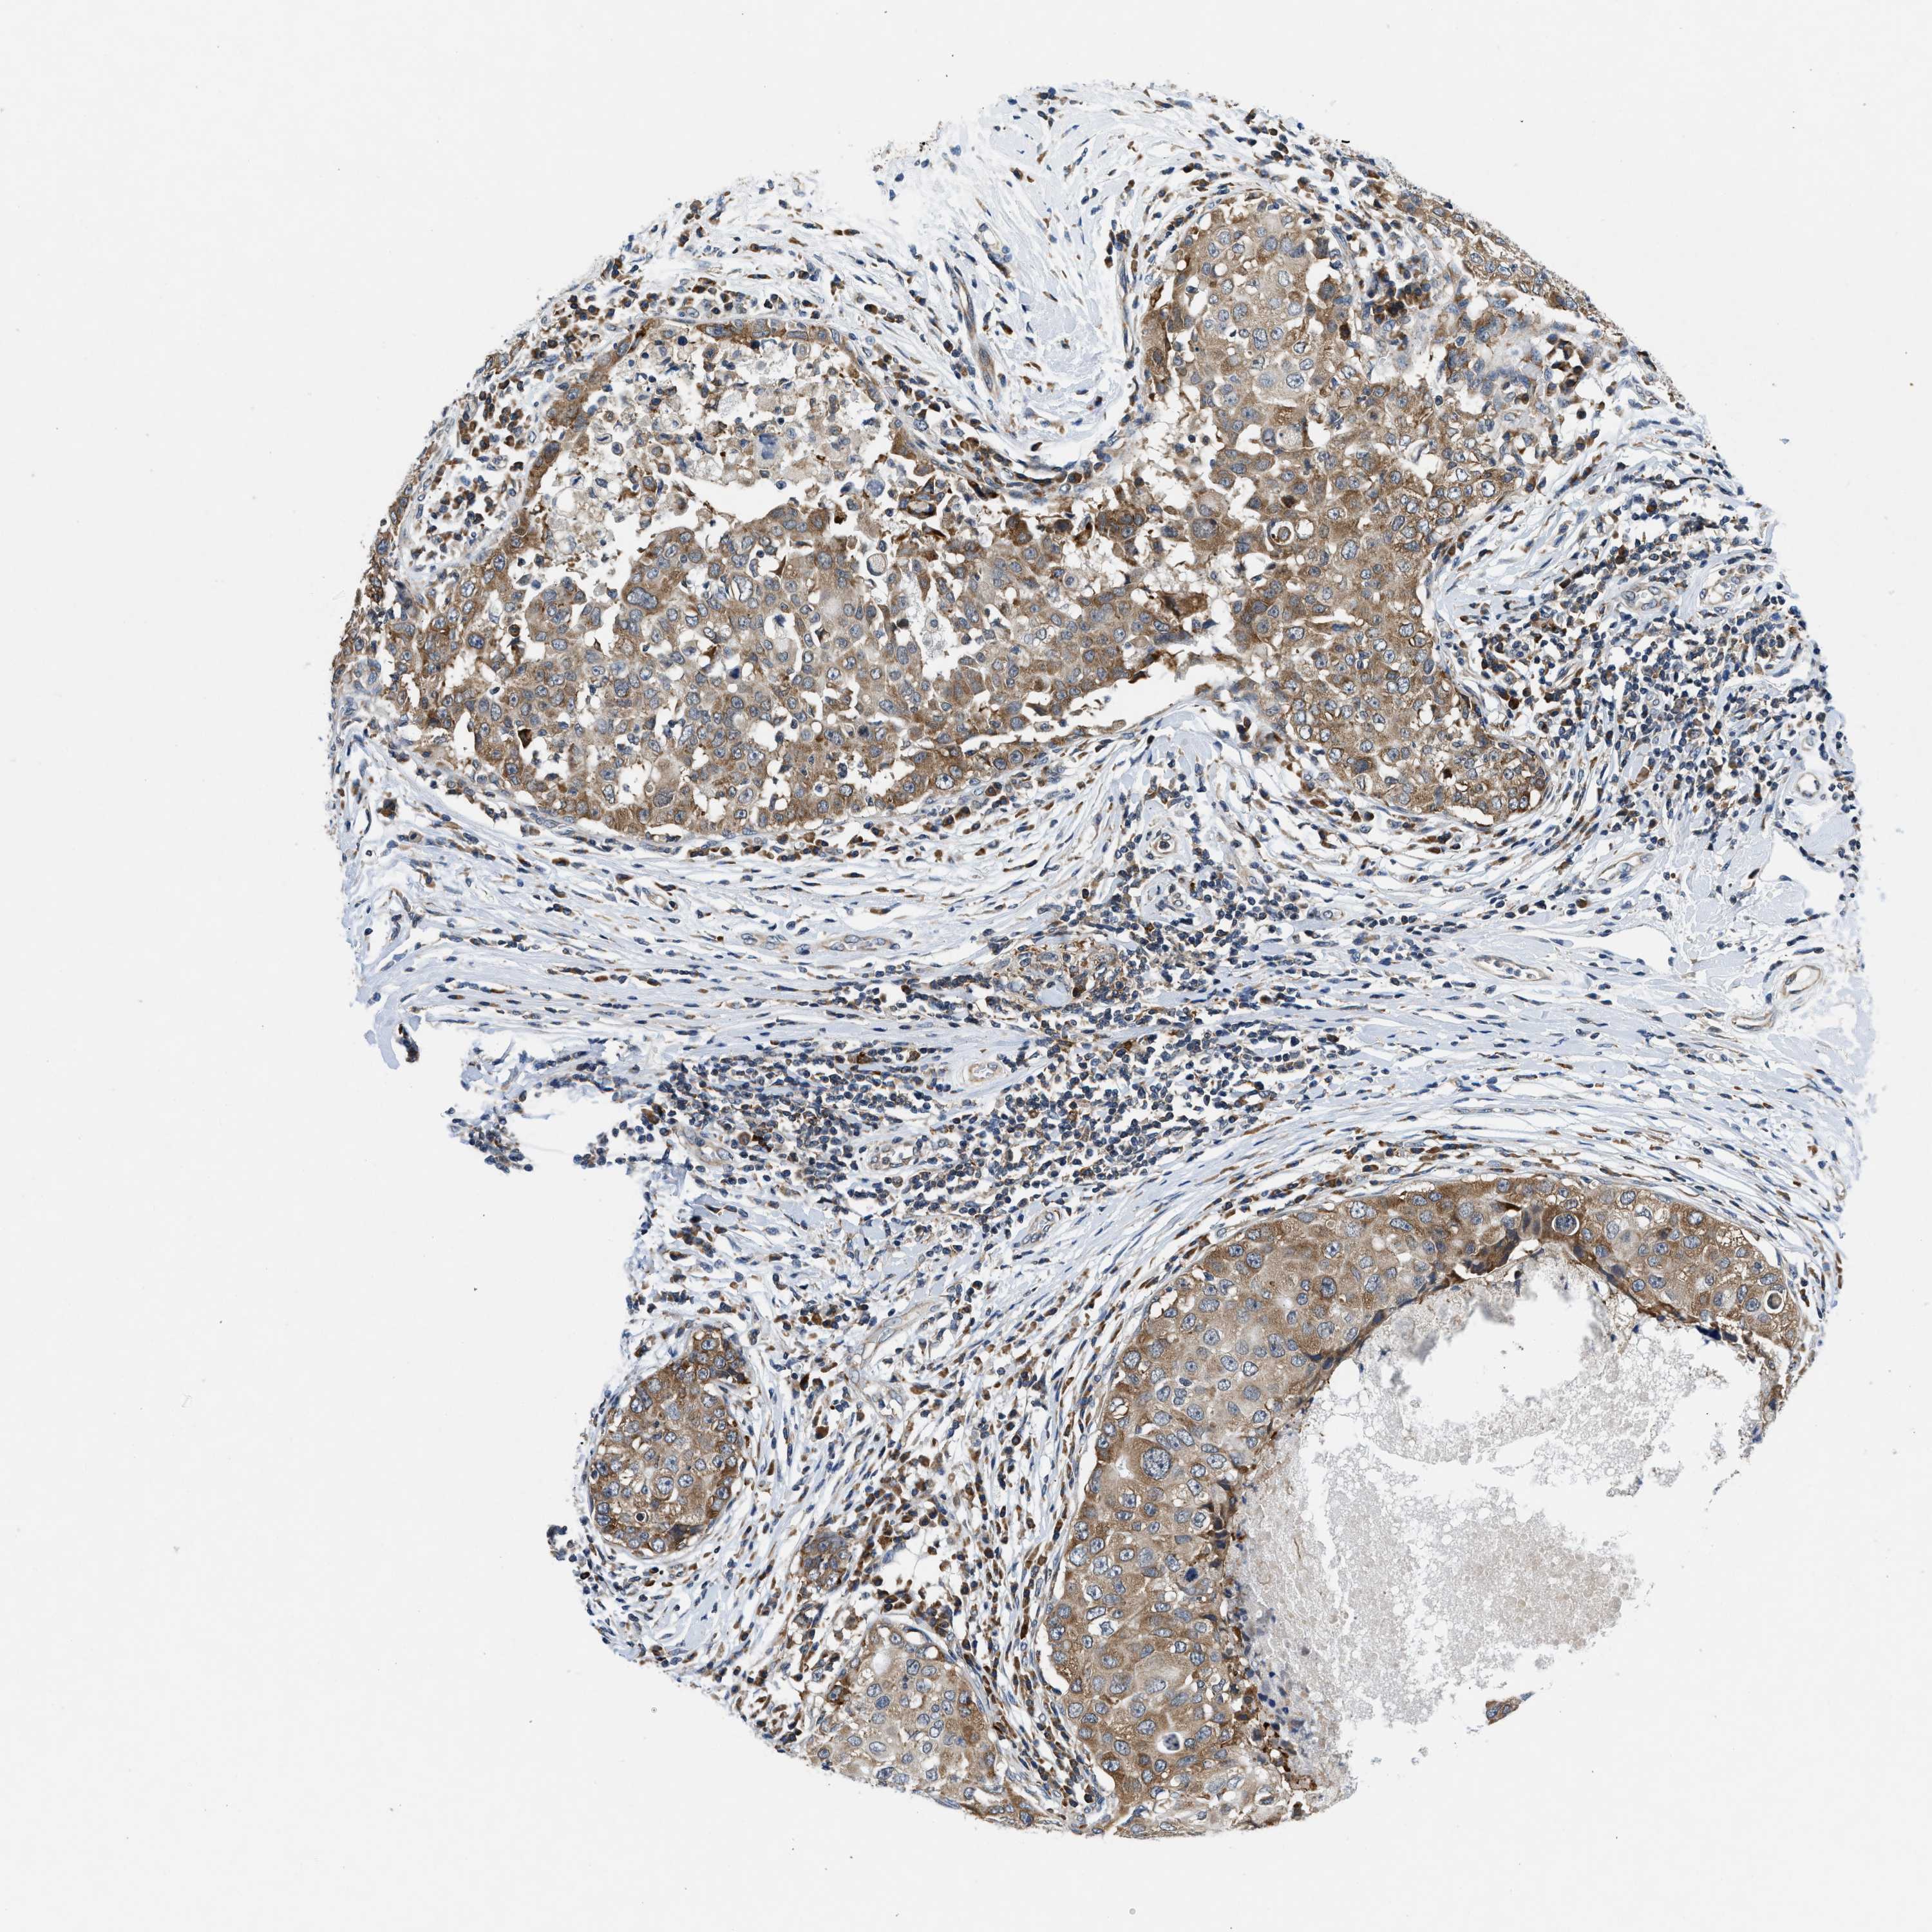

CANCER BREAST CANCER Show tissue menu

Breast cancer

Human cancer